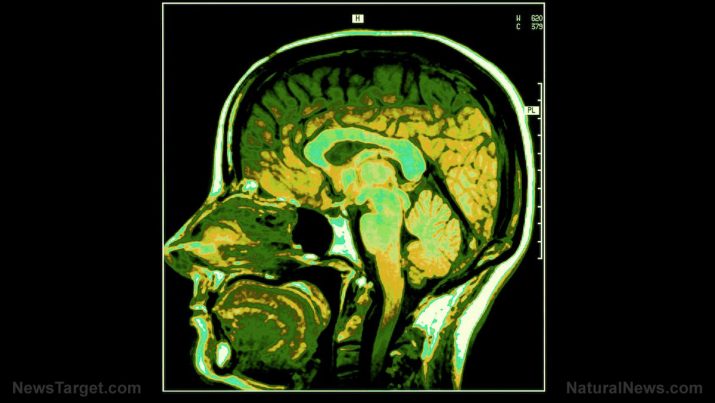

The term glioma refers to certain tumors that originate from the brain. A third of brain tumors are gliomas, and they start from the glial cells around the brain. These include astrocytes, oligodendrocytes, and ependymal cells. The tumors are called intra-axial brain tumors, as they grow within the substance of the brain and mix with normal brain cells.

One type of glioma, called the oligoastrocytoma, is composed of more than one kind of glial cell; thus, some refer to it as mixed gliomas. In mixed glioma, oligodendrocytes and astrocyte rapidly increase, forming a mass.

A mixed glioma – also referred to as an oligoastrocytoma – is a tumor made up of more than one kind of glial cell and is often found in the cerebellum. The brain and its surrounding tissue feel added pressure once the tumor develops, severely restricting blood flow and damaging brain cells.